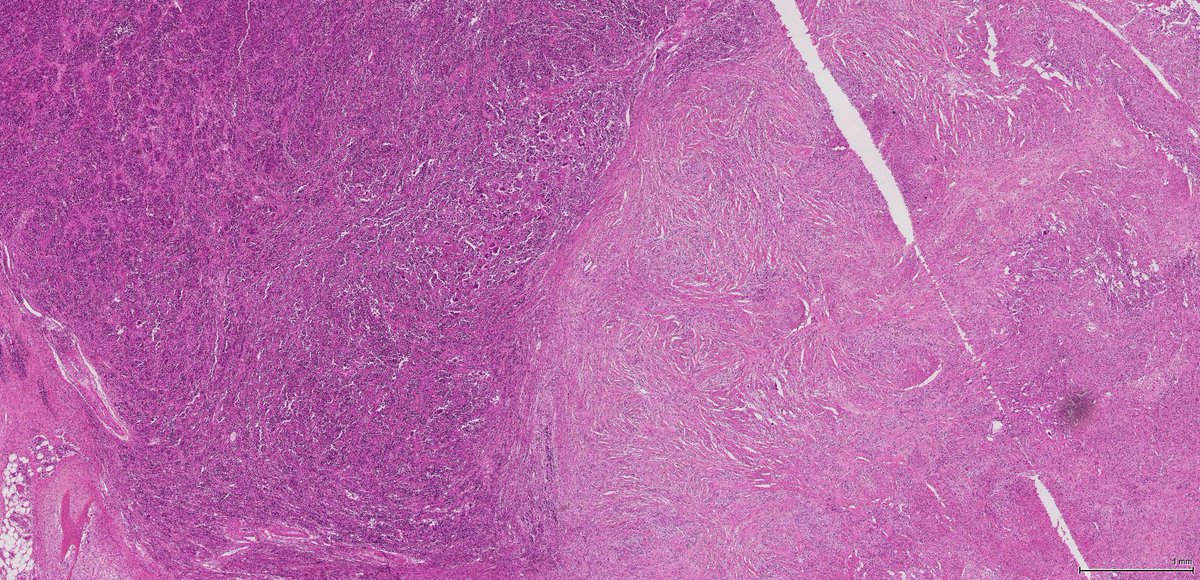

Desmoid-Type Fibromatosis

#OnePathboardPointAtATime • Locally-aggressive clonal myofibroblasts • Long, sweeping fascicles • Infiltrative growth • Collagenous stroma • Bland spindle cells • Low N:C ratio • Elongated ovoid nuclei • May have hyalinized or edematous areas pic.twitter.com/3bRBiakb66